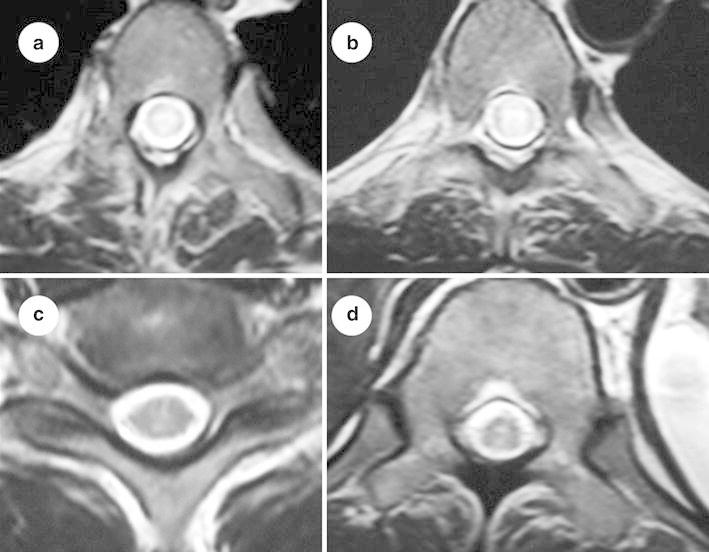

Fig. 3.

T2-weighted MRI of thoracic spine (axial section) showing poorly delineated intramedullary hyperintense lesion (a, b, c, d). There is no cord expansion